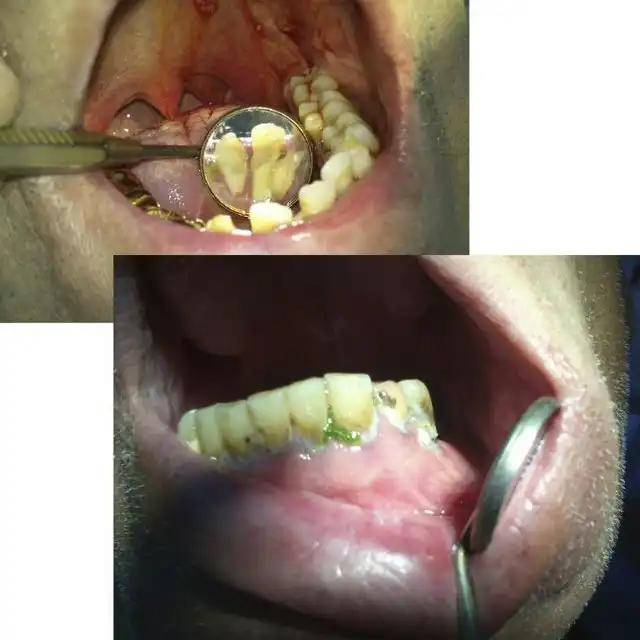

Угадайте, а сколько лет этому пациенту? По понятным причинам я не фотографировал его лицо полностью… Изначально он обращался около двух месяцев назад с переломом нижней челюсти в области суставного отростка слева, и шины наложить ему не могли, т.к. зубов целых почти нет… Был направлен в областную больницу, где походил с пращевидной бинтовой повязкой, и был отпущен домой… Остеосинтеза никто ему не делал. А потом спустя месяца два попал ко мне, после того как у себя на работе упал и ударился тем же местом)))) Очень «правдоподобно»… Но не в этом суть, парню 25 лет!!! Считает, что зубы разрушены, т.к. он на вредном производстве на заводе работает. Но гораздо более вероятная причина — нежелание чистить зубы. На фотографии видно, сколько там налета. И так многие выдумывают самые невероятные причины: работа с кислотой, жизнь в тайге, дальние плаванья, утрата зубов за один месяц после родов и т.п. Все это может повлиять в какой-то степени, но на деле у всех этих пациентов ужасная гигиена и последнее посещение стоматолога при царе Грохе. А у нашего парня зато татуха на всю правую руку, и на то, чтоб ее сделать, он нашел и время, и деньги, и желание… Это наш менталитет… Ездить на дорогой машине, понаделать татух, пирсинг, ходить в дорогих шмотках, но при этом с грязными ушами и нечищеными зубами. Редко кто на приеме попадается с таким уровнем гигиены, чтоб можно было стоматологическое вмешательство проводить. Да-да, есть индекс гигиены специальный, и если он выше определенной величины, то удалять нельзя. Но на деле удаляю, т.к. если строго подходить, то принять можно будет 2-3 человек за смену, остальных отправлять чистить зубы… Но потом люди приходят и с удивлением спрашивают, почему лунка после удаления болит? Никому даже в голову не приходит, что одной из вероятных причин может быть помойка во рту… Так что, друзья, идете к стоматологу — почистите зубы хорошенько ( да и вообще их чистить надо)), даже этой мелочью вы обеспечите себе хорошее отношение врача, потому что чистый рот — большая редкость и приятная неожиданность для стоматолога( к сожалению).

А это его панорамная рентгенограмма. То, что обвел красным, надо удалять. В 25 лет этому парню надо ставить съемные пластиночные протезы. Это такие, как вы видели у своих бабушек и дедушек в стаканах на тумбочке у кровати…